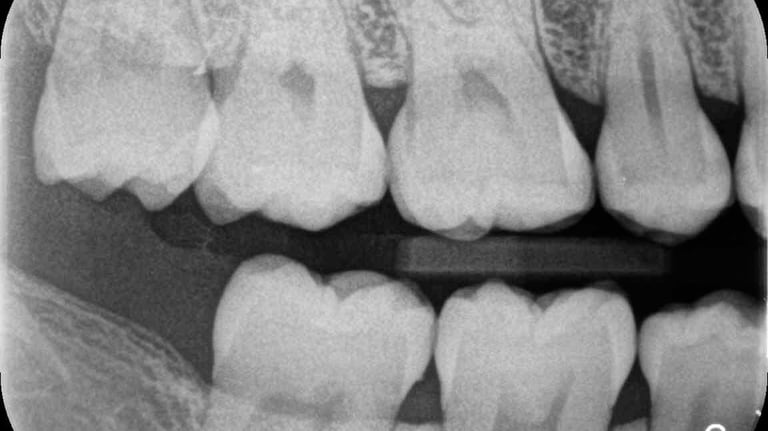

RADIOGRAFIA INTERPROXIMAL